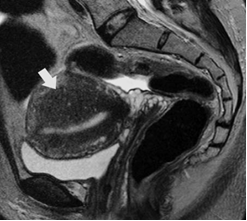

Các trường hợp có nghi ngờ lạc tuyến trong cơ tử cung trên nội soi đều được siêu âm màu và chụp cộng hưởng từ nhân để khẳng định chẩn đoán bởi các bác sĩ khoa chẩn đoán hình ảnh bệnh viện ĐHYD đảm nhận.

MRI nghi tổn thương Adenomyosis |